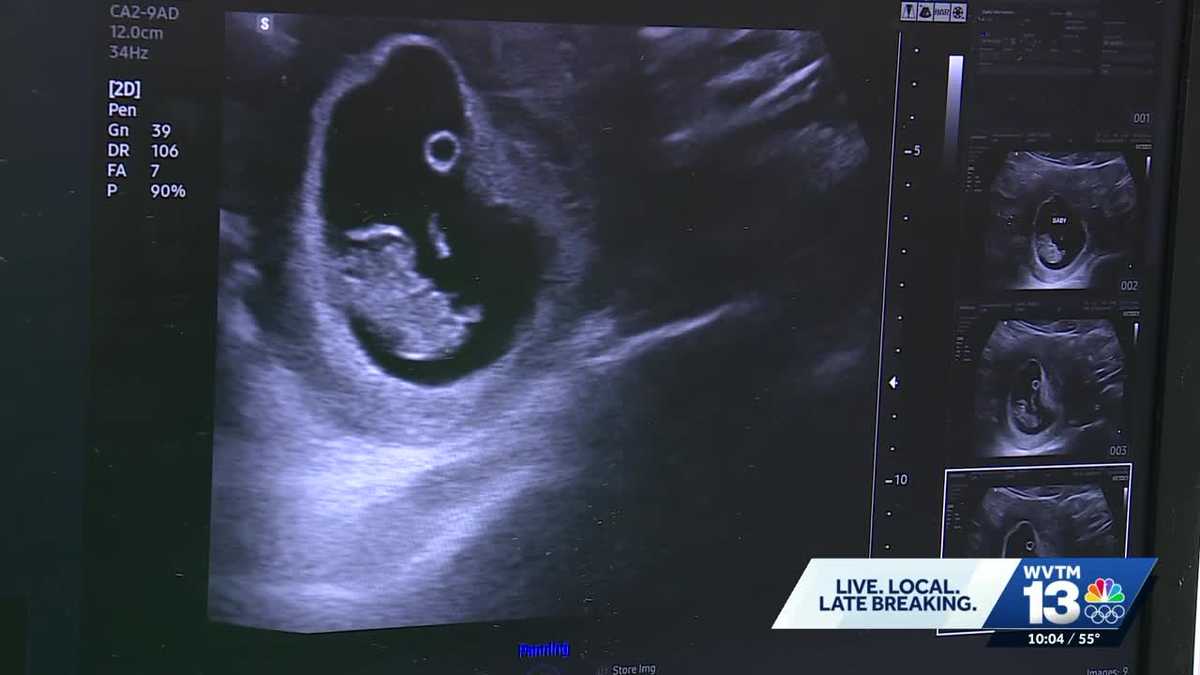

Dr. Mehmet Oz recently highlighted Alabama’s plan to use robots for ultrasounds due to a shortage of OB-GYNs during a rural healthcare roundtable with White House officials, a statement that has sparked significant attention on social media.

The initiative is part of Alabama’s use of the $203 million awarded under the federal government’s Rural Health Transformation Program, which was created in the Big Beautiful Bill.

According to the grant proposal, Alabama intends to allocate some of the funding for digital obstetric regionalization and telerobotic ultrasound. However, OB-GYNs in the state expressed skepticism about the plan’s effectiveness.